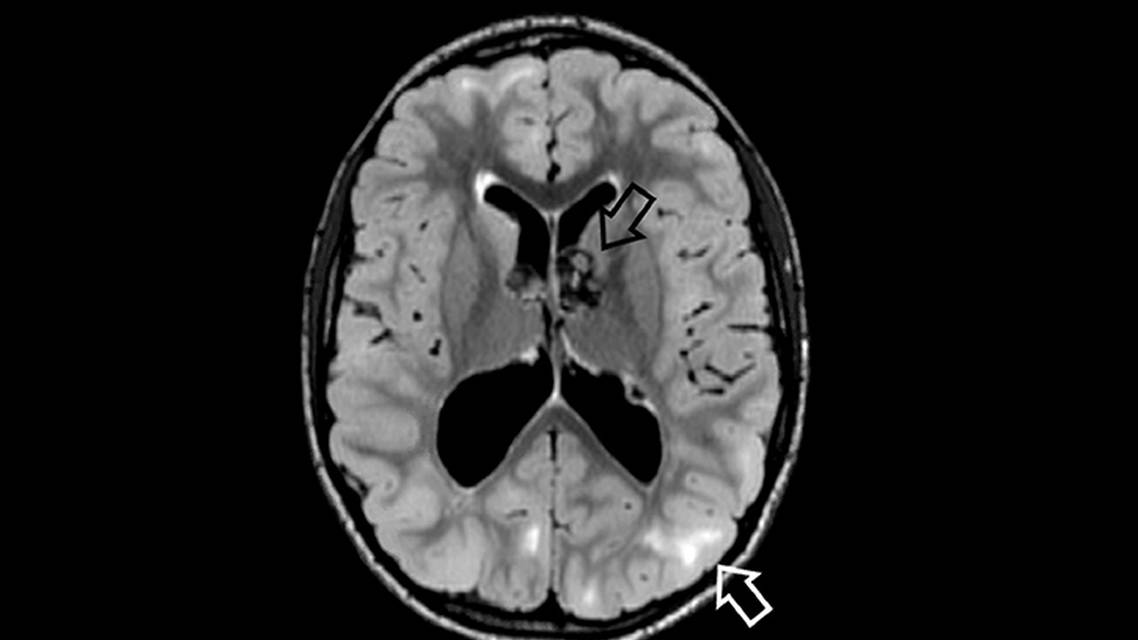

Brain MRI shows cortical tubers in up to 90% of affected individuals (Figure). Focal cortical dysplasia and cerebral white matter radial migration lines are also seen. Up to 80% of cases also have subependymal nodules along the lateral and third ventricles, sometimes described as appearing like dripping candle wax. These nodules can transform into subependymal giant cell astrocytomas (SEGAs; 15% of cases), which increases risk of obstructive hydrocephalus. Subependymal nodules typically do not occur after age 20.7